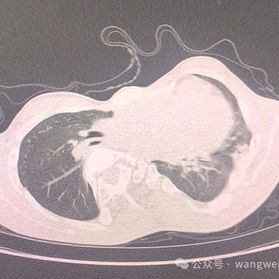

Preoperative Examination

The anterior chest wall exhibited severe complex deformities, manifesting as an overall depression but protrusions at the sternal manubrium and xiphoid process. The lower portion of the chest wall showed an irregular, uneven surface. The heart was significantly compressed, with an oxygen saturation of only 75% without supplemental oxygen. Severe scoliosis was also present.